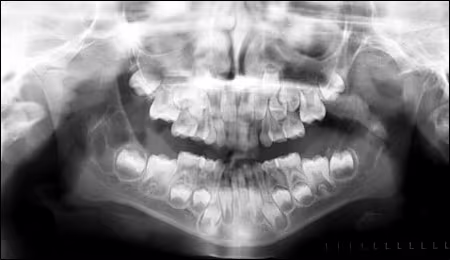

The initial radiographic survey from three years earlier is seen in Figure 1.

Figure 1. Panoramic radiograph taken in December 2004. The lesions are already present bilaterally at this time.

The lucent area in the right mandibular ramus was clearly visualized with a multilocular appearance. The lesion in the left ramus was somewhat diffuse and more difficult to localize.